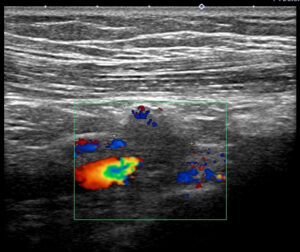

これが、実際のエコー像

私を唸らせたのは

理由1.まずこのリンパ節(鎖骨下リンパ節)が「明らかに節外浸潤」している点

理由2.(理由1以上に私を悩ませたのが)鎖骨下静脈と距離がない=少なくとも「簡単には剥がせない」

このColor Doppler の左やや下から入ってくる「太い赤(内部に黄緑青)」が鎖骨下静脈です。

鎖骨下リンパ節と、この鎖骨下静脈が(エコーで見て)非常に近いのです。